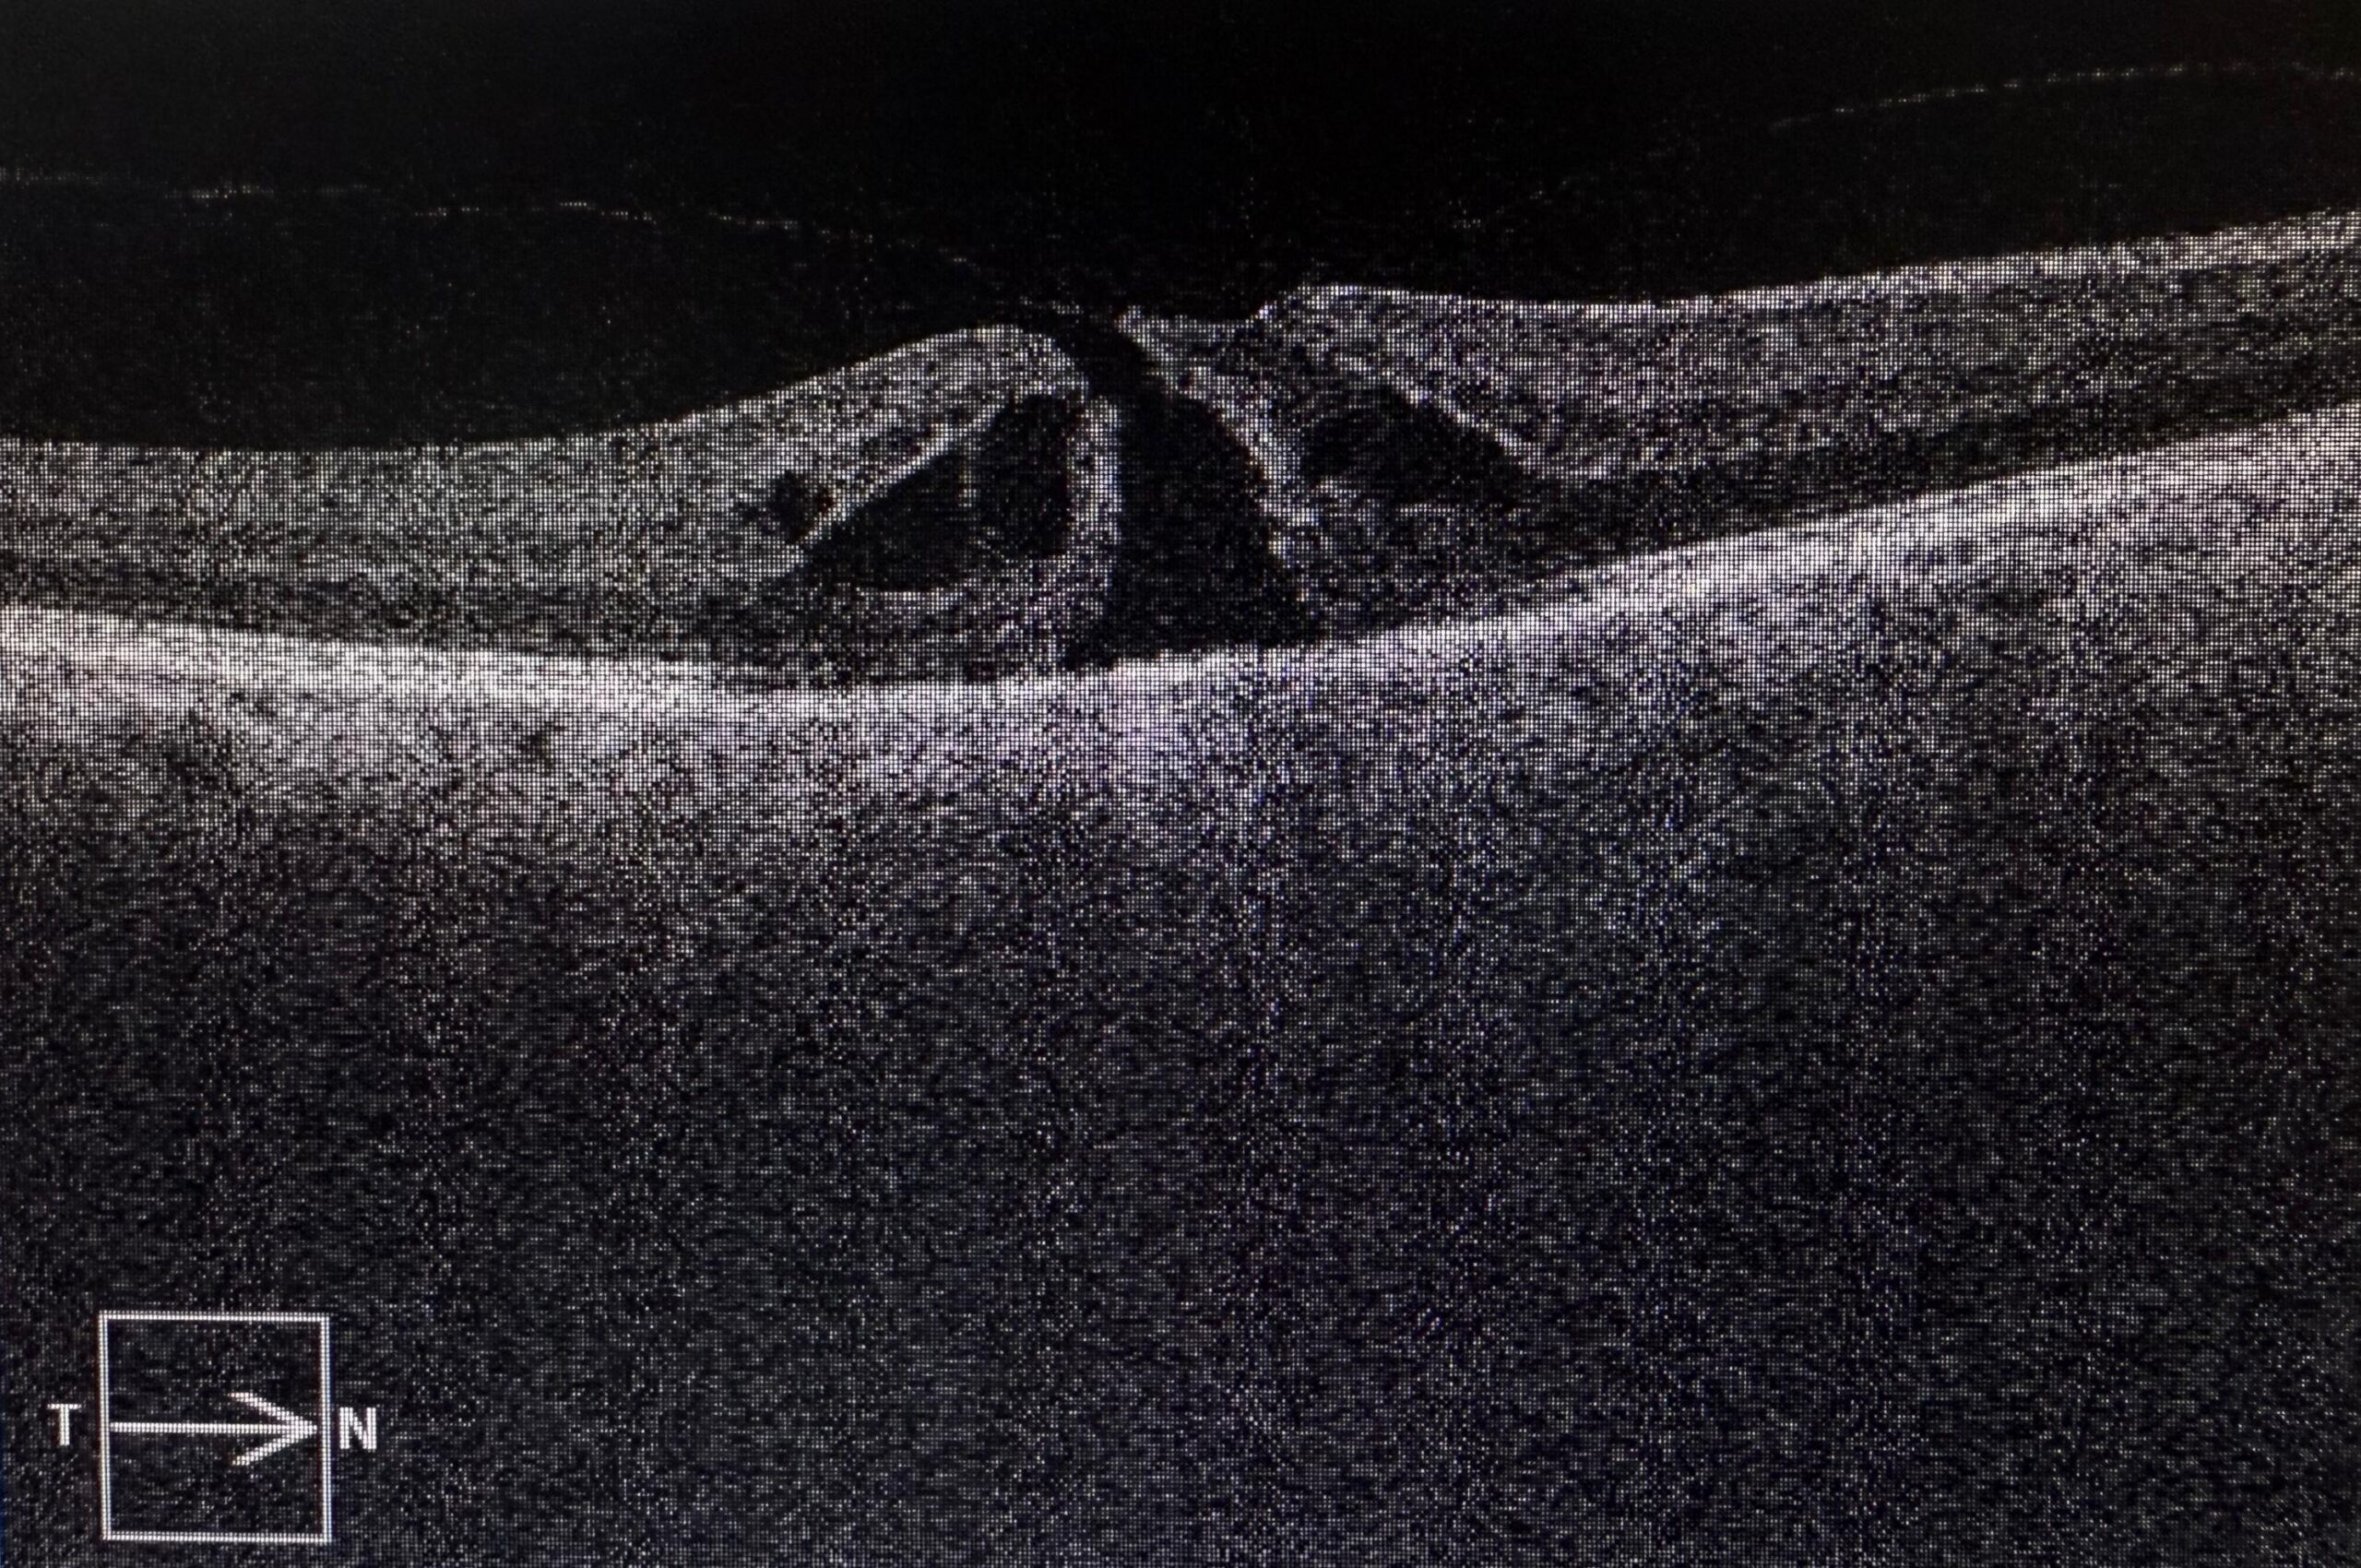

Accurate diagnosis is the foundation of successful retinal care. Our centre is equipped with the latest imaging modalities to detect and monitor retinal diseases with unparalleled precision.

Together, these imaging systems allow us to detect diseases early, plan accurate treatment, and track response to therapy effectively.

OCT scan, Retinal Photography, FFA, and B-Scan.

Diabetic Retinopathy, Retinal Detachment, Macular Hole, ERM, Vitreous Hemorrhage.